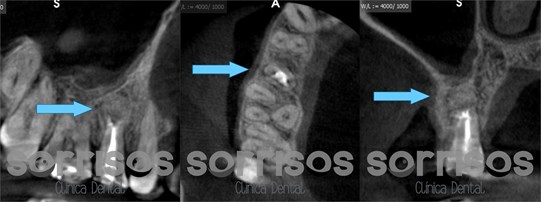

Semanas después del tratamiento no hay síntomas de dolor a palpación o percusión. En el control a los 6 meses, se hace un nuevo CBCT y se observa parte del biomaterial que se va reabsorbiendo, pero también regeneración ósea con recuperación de la cortical ósea vestibular: